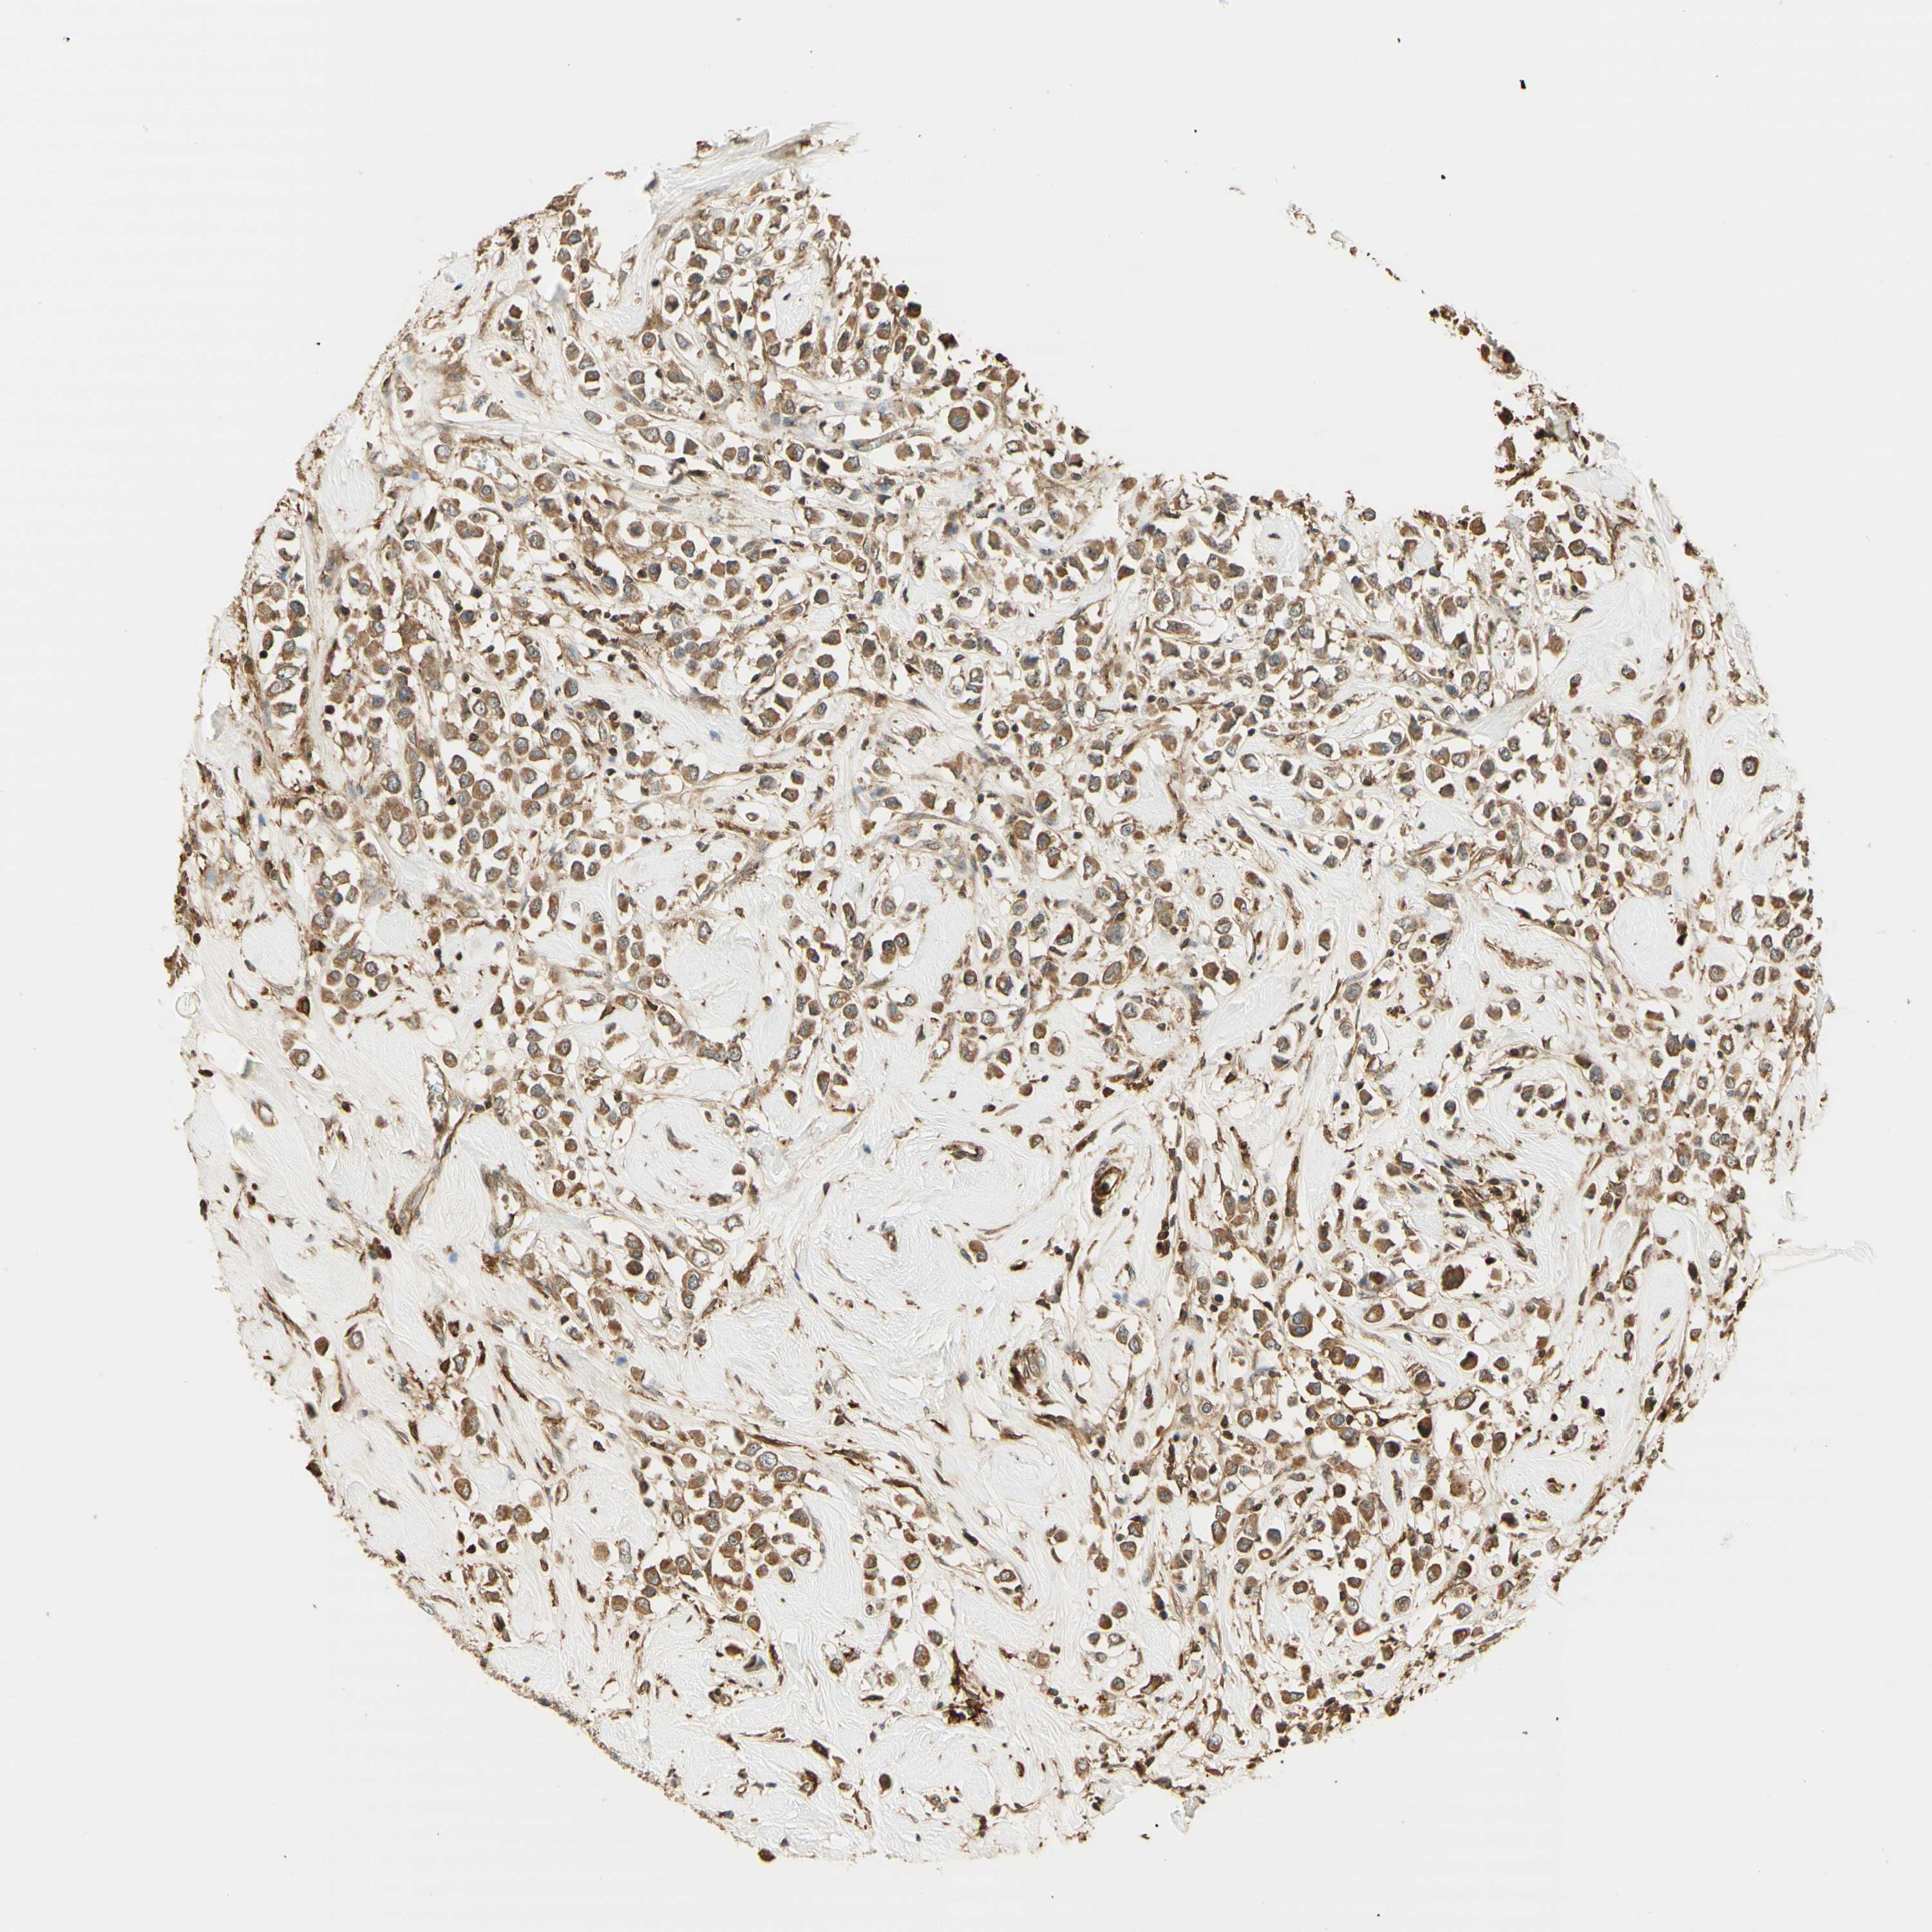

CANCER BREAST CANCER Show tissue menu

BRCA TCGA BRCA VALIDATION PROTEIN EXPRESSION

ANTIBODIES

AND

VALIDATION